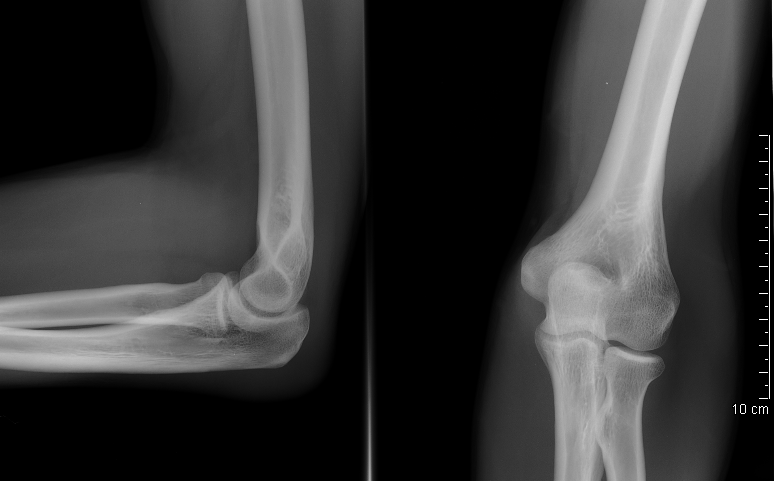

Los principales tipos de imágenes diagnósticas incluyen rayos X, tomografías computarizadas (TC), resonancias magnéticas (RM), ecografías y estudios de medicina nuclear, como las gammagrafías.